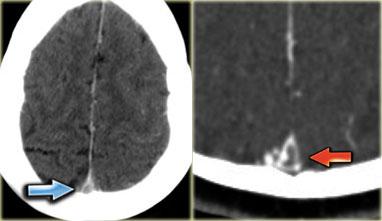

Dấu hiệu cục máu đông tăng tỷ trọng (2)

Hình ảnh tĩnh mạch vỏ não bị huyết khối biểu hiện dưới dạng một dải hoặc đường tăng tỷ trọng hình dây thừng còn được gọi là dấu hiệu dây thừng (cord sign).

Một thuật ngữ khác thường được sử dụng là dấu hiệu mạch máu tăng tỷ trọng (dense vessel sign).

Dấu hiệu cục máu đông tăng tỷ trọng (3)

Hình ảnh bên trái là của một bệnh nhân có nhồi máu xuất huyết ở thùy thái dương (mũi tên đỏ).

Lưu ý xoang ngang tăng tỷ trọng do huyết khối (mũi tên xanh dương).